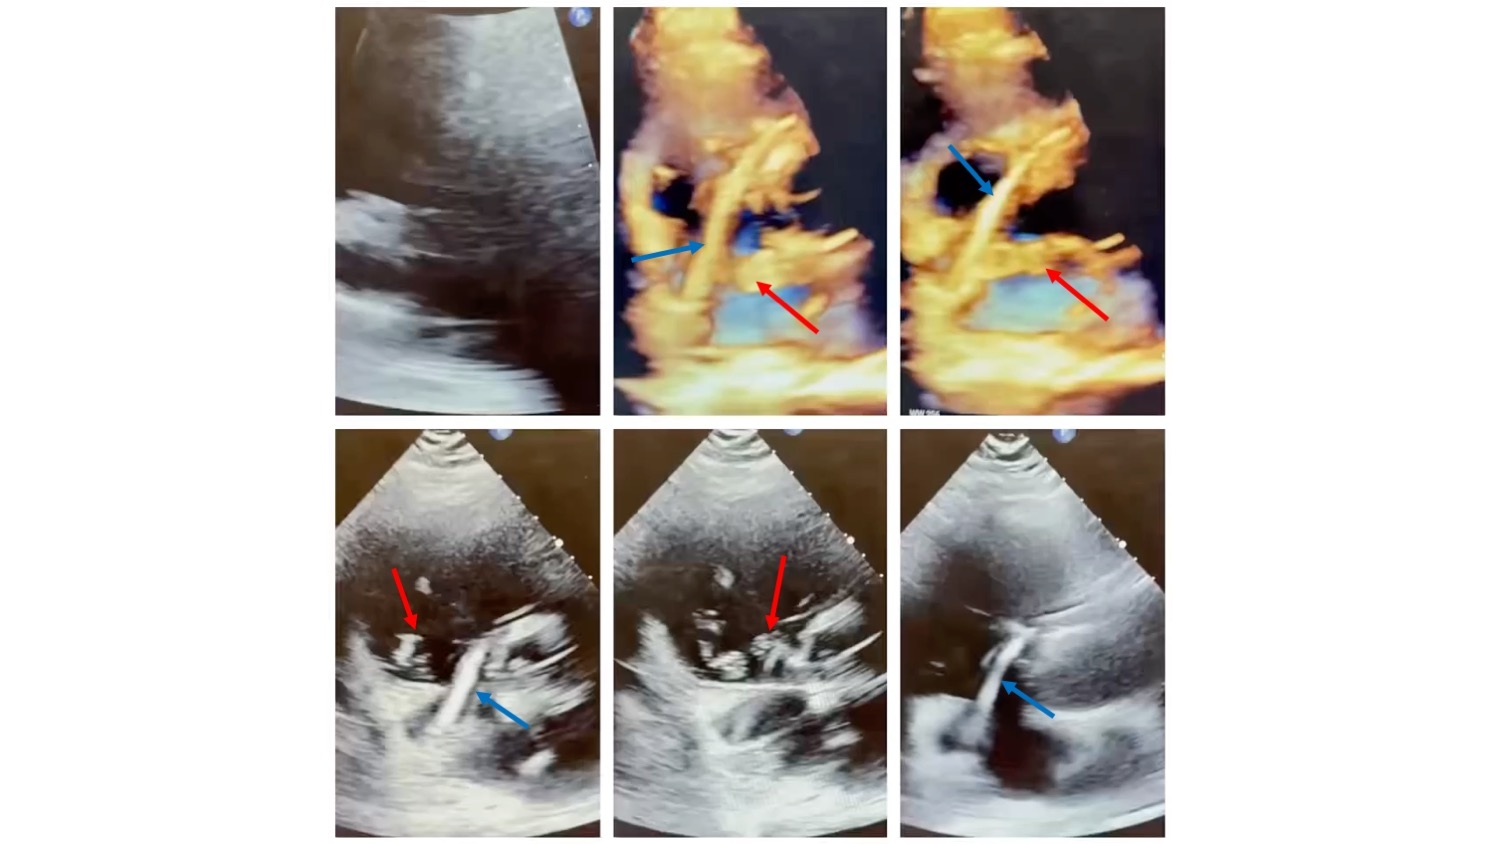

A 69-year old nursing home resident, bedbound from a previous motor vehicle accident and multiple lumbar fusions presents with sudden onset shortness of breath. On initial evaluation, the patient was hypoxic requiring high flow nasal cannula and point of care ultrasound echocardiography showed a CIT (Figure 1). CT PE showed extensive bilateral PE’s with a CIT in the RA (Figure 2). PERT decision was made to take the patient for urgent thrombectomy with ECMO backup.

Peri-procedure TTE guidance was utilized to assist with retrieval of the CIT, and a sizable thrombus straddling a patent foramen ovale going from the right to left atrium was noted. Given the patient’s prohibitive surgical risk as determined by CTS, the decision was made to proceed with thrombectomy and percutaneous removal of the CIT with 3D echocardiographic guidance (Figure 3). At the conclusion of the case, all thrombus was successfully removed with the INARI FlowTriever 24 Fr catheter from bilateral pulmonary arteries in addition to the CIT extending from the right to left atrium that was retrieved utilizing the INARI FlowTriever 20 Fr Curved catheter (Figure 2). The patient was monitored in the CCU and then discharged several days later to a skilled nursing facility in stable condition.